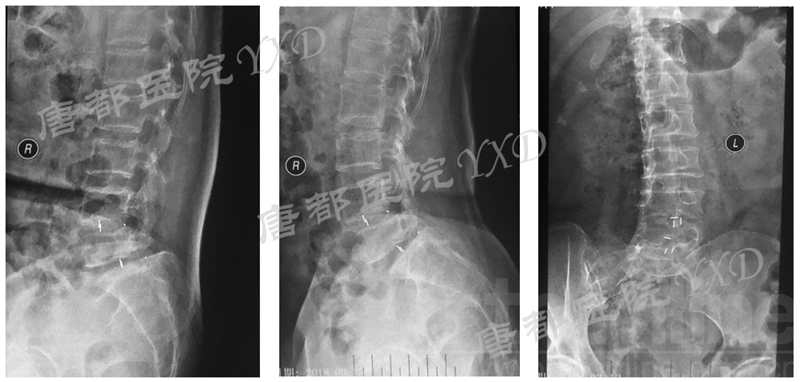

影像学检查:

诊断:腰椎椎间融合术后融合器后移

手术方案:显微镜辅助MI-TLIF腰椎翻修术